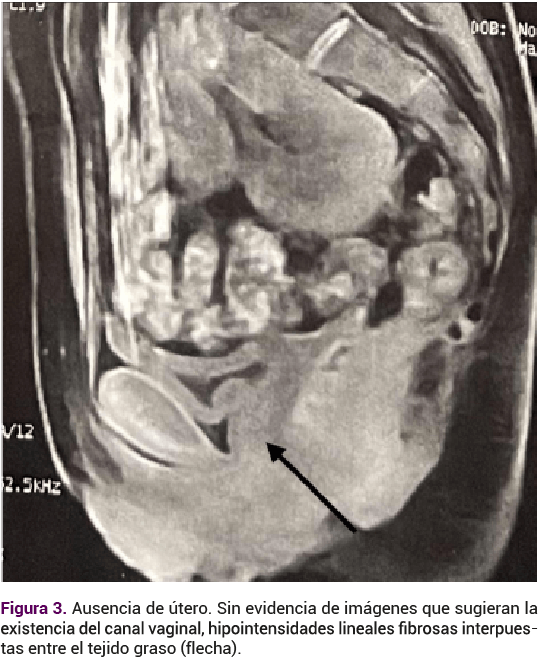

El ultrasonido renal reportó ectopia renal cruzada, de apariencia fusionada con el uréter distal único. El ultrasonido pélvico reportó la ausencia del útero y de los ovarios. El perfil hormonal se informó con: FSH 4.39 mUI/mL, LH 2.89 mUI/mL, estradiol 80.5 pg/mL, androstenediona 1.27 ng/mL, testosterona total 0.2 pg/mL, prolactina 14.2 ng/mL, TSH 1.1 mUI/mL. La resonancia magnética reportó: ausencia de útero, ambos ovarios con desplazamiento cefálico, sin evidencia de imagen que sugiriera el canal vaginal (Figura 3). Riñón único intrapélvico parasagital izquierdo (Figura 4) con diagnóstico por imagen tomográfica de ectopia renal cruzada y agenesia úterovaginal.

Aplasia congénita del útero y la parte superior (2/3) de la vagina en mujeres con desarrollo normal de caracteres sexuales secundarios y un cariotipo normal de 46, XX. La agenesia vaginal completa ocurre en el 75% de los casos mientras que el 25% restante tiene una vagina reducida.10